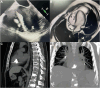

We report a case of intracardiac cement embolism in a 24-year-old male patient as a rare postprocedural complication of percutaneous vertebroplasty. The patient was assessed 1 month after the procedure because of persistent tachycardia. Computed tomography scans showed an intracardiac mass in both the right atrium and right ventricle. After thorough multidisciplinary discussion, the patient was subsequently managed conservatively in conjunction with serial imaging and close surveillance.